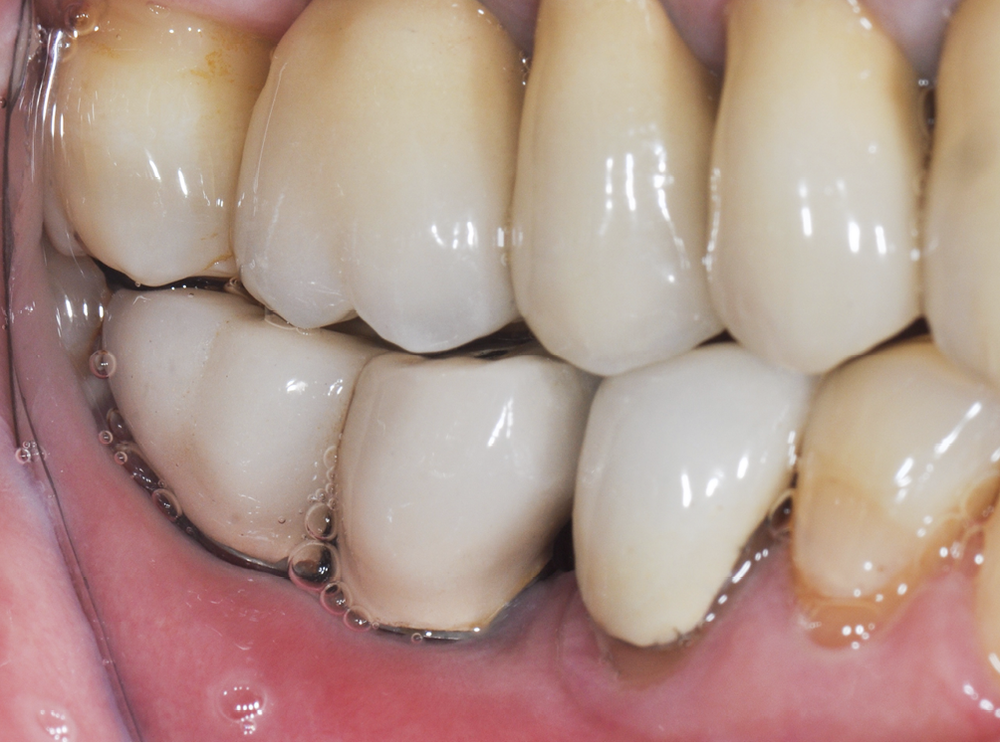

– la mucosite péri-implantaire, définie comme une inflammation réversible des tissus mous péri-implantaires sans atteinte osseuse (fig. 1a, b) ;